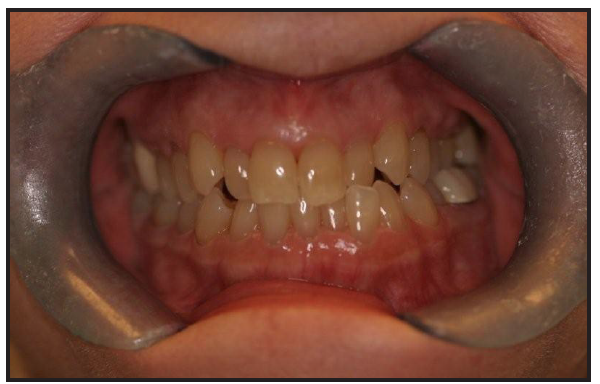

When a patient has been a part of a dental practice for some time, the patient may express interest in new goals for their smile. In this particular case, the patient asked if there was technology available to show her what the possibilities would be for a new, white smile. The patient expressed to the PCC that she has a book signing coming up for a recently published, fictional novel. The patient also explained that the villain in her book is described as having yellow, scraggly teeth, and when she looks in the mirror, she sees herself as that villain (see Figure 1 and Figure 2). After listening closely, the PCC discussed smile simulation technology. Smile simulation technology software allows the patient to see the possibilities available to them in cosmetic design before any treatment is completed. When using this technology, a digital image of the patient is obtained and downloaded into the software. Then a library of different smiles is superimposed and viewed using the patient's image. This approach helps a patient visualize the end result and take ownership in the chosen outcome.

Figure 1 – Initial Patient Photo

Figure 1

Figure 2 – Initial Photo Using Retractors

Figure 2